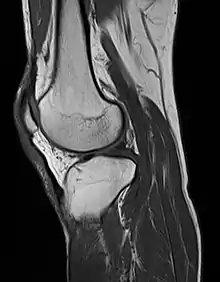

MRI uses strong magnetic fields to align atomic nuclei (usually hydrogen protons) within body tissues, then uses a radio signal to disturb the axis of rotation of these nuclei and observes the radio frequency signal generated as the nuclei return to their baseline states.[8] The radio signals are collected by small antennae, called coils, placed near the area of interest. An advantage of MRI is its ability to produce images in axial, coronal, sagittal and multiple oblique planes with equal ease. MRI scans give the best soft tissue contrast of all the imaging modalities. With advances in scanning speed and spatial resolution, and improvements in computer 3D algorithms and hardware, MRI has become an important tool in musculoskeletal radiology and neuroradiology.

One disadvantage is the patient has to hold still for long periods of time in a noisy, cramped space while the imaging is performed. Claustrophobia (fear of closed spaces) severe enough to terminate the MRI exam is reported in up to 5% of patients. Recent improvements in magnet design including stronger magnetic fields (3 teslas), shortening exam times, wider, shorter magnet bores and more open magnet designs, have brought some relief for claustrophobic patients. However, for magnets with equivalent field strengths, there is often a trade-off between image quality and open design. MRI has great benefit in imaging the brain, spine, and musculoskeletal system. The use of MRI is currently contraindicated for patients with pacemakers, cochlear implants, some indwelling medication pumps, certain types of cerebral aneurysm clips, metal fragments in the eyes and some metallic hardware due to the powerful magnetic fields and strong fluctuating radio signals to which the body is exposed. Areas of potential advancement include functional imaging, cardiovascular MRI, and MRI-guided therapy.